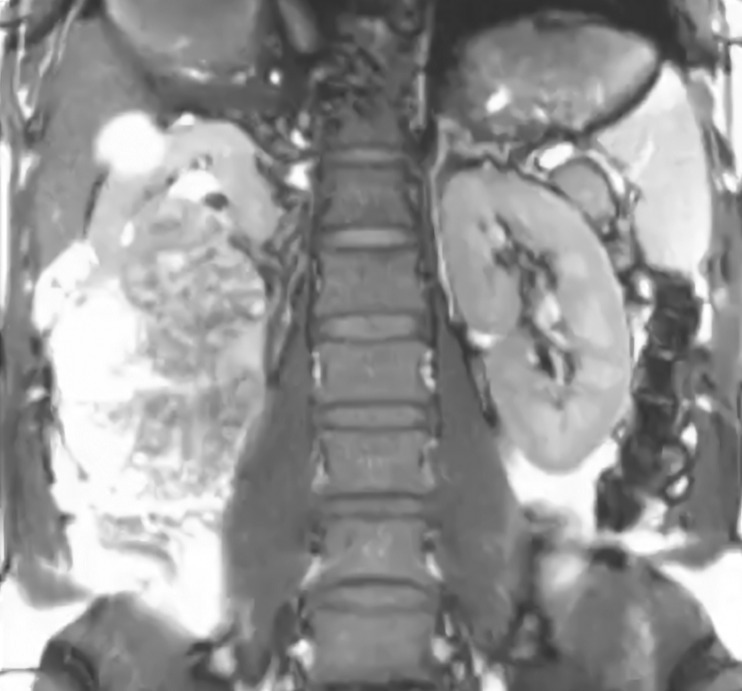

Precisó que, para diagnosticar este tipo de cáncer, en el ISSSTE están disponibles estudios de laboratorio, como biometría hemática, química sanguínea, en el primer nivel de atención, mientras que en el segundo nivel, se pueden realizar tomografías, resonancias magnética, y en el tercer nivel se brinda el servicio de radioterapia.

“Se ha fortalecido la detección de esta enfermedad, hay mayor número pruebas de laboratorios disponibles, se ha incrementado el número de salas de ultrasonido, de tomografía, resonancias, de quirófanos, incluso”, agregó.